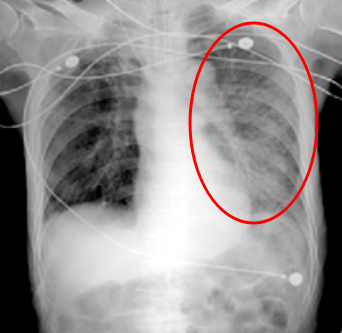

그리고 x레이 촬영으로 폐에 염증이 있는지 확인을 합니다. 폐는 공기가 왔다갔다 하기 때문에 x레이 촬영을 하면 검게 보이는데 폐에 염증이 생기거나 물이차면 폐가 하얗게 보이죠.

빨간 동그라니 부분이 폐렴. 출처: 질병관리청 또는 폐 CT 촬영을 통해 조금 더 자세히 볼 수 있는데 CT검사를 통해 폐렴의 정확한 위치와 범위 등을 확인할 수 있습니다.